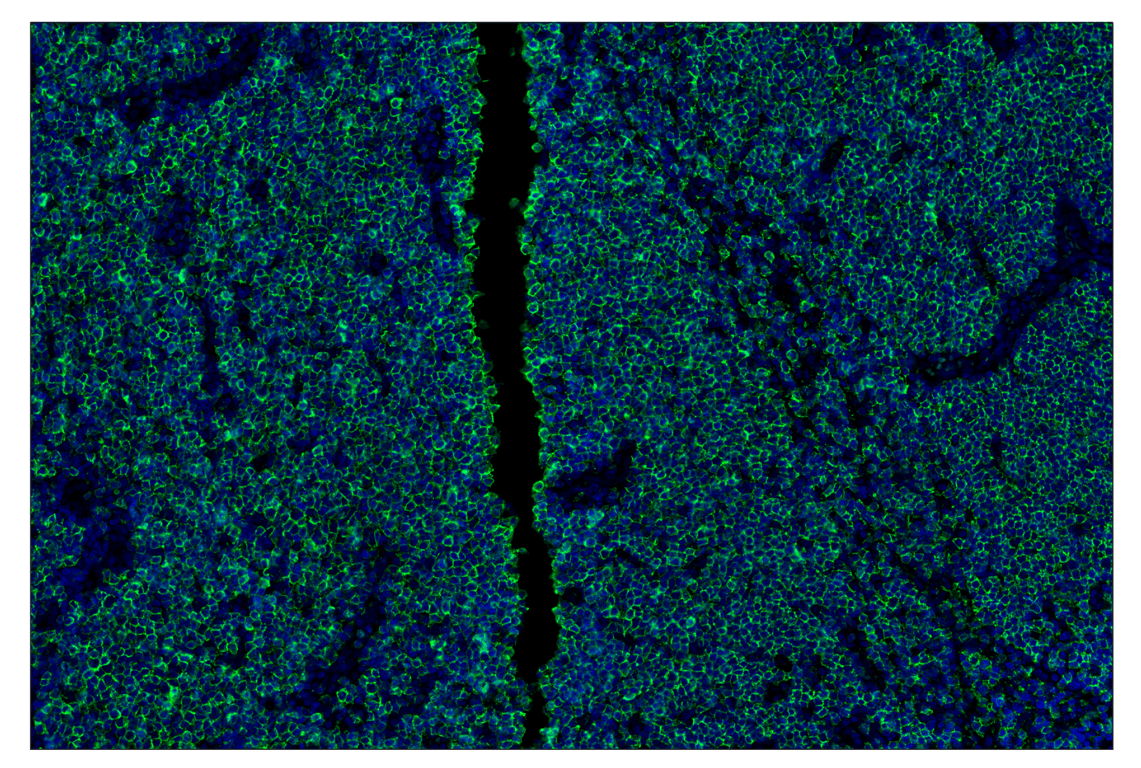

Figure 1. All antibodies in your plex size of choice (3-8 maximum unique oligo-conjugated antibodies) are added in cocktail in one primary incubation step. Complementary oligos with fluorescent dyes (channels: 488, 594, 647, and 750) amplify the signal of up to 4 oligo-conjugated antibodies in the first round of imaging by building oligo-fluorophore constructs attached to the antibody. If the plex size is greater than 4, the first round of oligos and fluorophores are gently removed, and a second round of amplification is performed to visualize up to 4 additional oligo-conjugated antibodies; the complementary oligo system and the use of the fluorophore removal process enables a second round of antibodies to be amplified from the same substrate, without cross-reactivity. The 2 images are then aligned and fused computationally with either proprietary or open-source software to generate an image consisting of up to 8 targets.